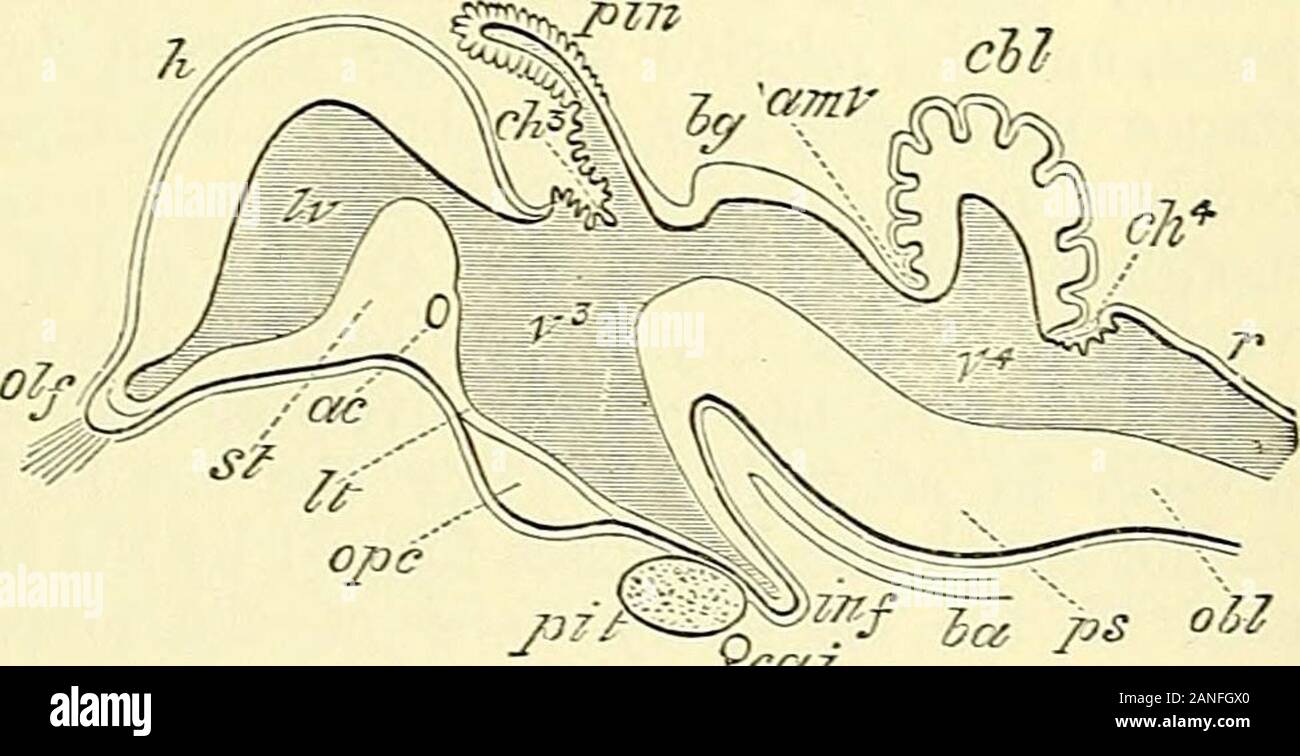

RM2ANFGX0–Quain der Elemente der Anatomie. ring Abb. 729.-op ein Bild. 729. Längsschnitt durch das Gehirn OFA KÜKEN VON ZEHN DATS. (Nach Mihalkovics.) h, zerebralen Hemisphäre; olf, oKactory lobe und Nerv; St, Corpus striatum; iv, lateralventricle; ac, anterior com-missure; Er, der Lamina terminalis; ope, Optic commissure; Grube, der Hypophyse; inf inf Undi-bulum; Cai, interne carotidartery; v^, dritten Ventrikel; ch?, Choroid plexus dritter Ventrikel; Pin, zirbeldrüse; Ijg, Korpora bigemina; amv, anterior medullary Velum; unten - n - hich zwei letzte Referenzen sind das Aquädukt von Sylvius und crur

RM2CH08HM–. Quains Elemente der Anatomie . Enient zu bringen Feige. 729. – UMRISS EINES LÄNGSSCHNITTS DURCH DAS GEHIRN OFA-KÜKEN VON ZEHN DATS. (Nach Mihalkovics.) h, zerebrale Hemisphäre ; Olf, olfaktorische Lappen und Nerven ; st,corpus striatum ; IV, lateralventricle; ac, anterior com-misure; Es, lamina terminalis;op, optic commissure ; Piit,pituitäre Drüse ; inf, infundi-bulum ; cai, interne cardartery ; ?••*, dritte Oticle ; Plexus ; Plexus ; Plexus ; Plexus hg, corpora bigemina ; amt anterior medullarj velum ;unter welchen zwei letzte Referenzen das Aquädukt von Sylvius und sind